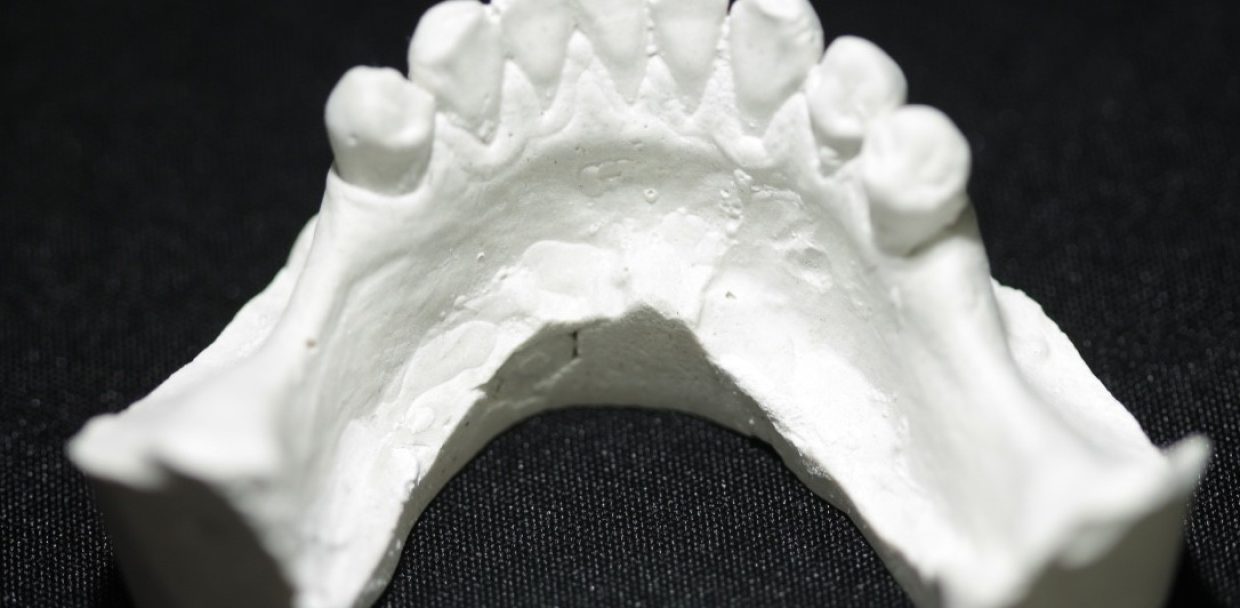

This case serves as an example of a Kennedy Class I

Kennedy Class I is a significantly challenging denture since it has a rotational fulcrum: Two flexible direct retention retainers are needed with the use of stress relief clasps that prevent torquing forces to the abutment.

Design for a case with long free end saddles.

The angulation of the teeth present a challenge with path of insertion.